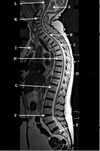

33

What is letter A?

L4-5 HNP

34

What is letter B?

S1 VERTEBRAL BODY

35

What is letter C?

L5 VERTEBRAL BODY

36

What is letter D?

L2-3 DISK SPACE

37

ABDOMINAL AORTA

38

INTERVERTEBRAL DISC

39

FACET JOINT

40

SPINOUS PROCESS

41

What is letter E?

LAMINA

42

What is letter F?

SUPERIOR ARTICULAR PROCESS

43

What is letter G?

SPINAL CANAL

44

What is letter H?

INFERIOR VENA CAVA

45

L4-5 INTERVERTEBRAL DISK SPACE

46

PEDICLE

47

NERVE ROOTS

48

CSF

49

ERECTOR SPINAE MUSCLE

50

FACET (ZYGAPOPHYSEAL) JOINT

51

52

53

What is letter J?

54

What is letter K?

PSOAS MUSCLE